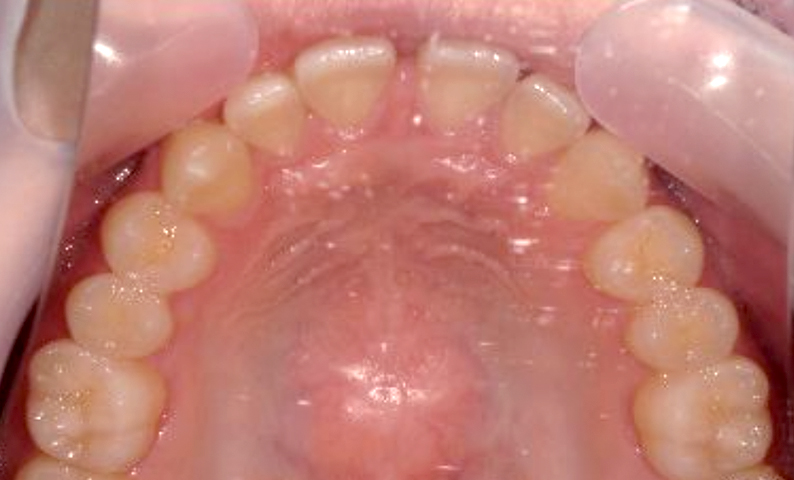

| 治療前 | 治療後 |

|---|---|

|